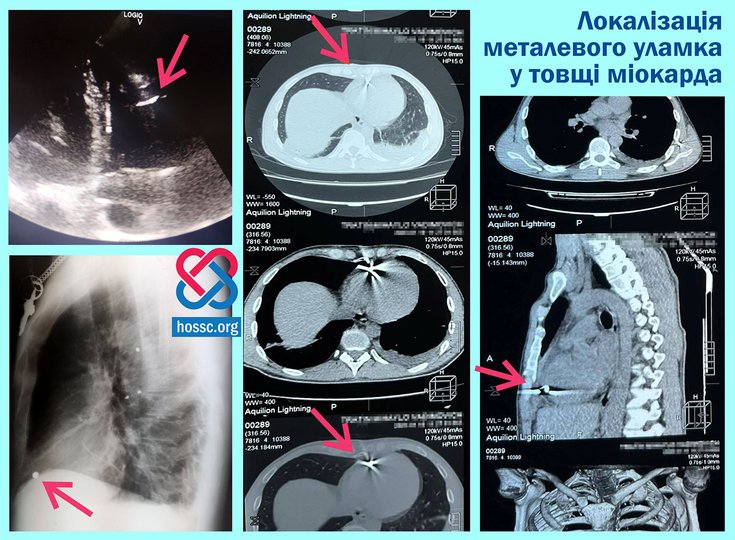

Було рекомендовано військовим лікарям, надаючи необхідну допомогу, щоб бути усуненим із спеціалізованої установи. Ось чому пацієнт увійшов у відділення хірургії серця в серцево -судинному центрі. Під час іспитів експерти визначали точне розташування фрагмента – в товщині серцевого м’яза правого шлуночка.

ЩоПісля проведення складної хірургії у відкритому серці, яка продовжувала боротися під час втручання, оперативна команда серця -хірурга Андреа Кланц та Валері Сухарев, помічник Анджеліни Гаврилова, анестезіолога Мікейла Ільніцького, що підтримує догляд. і провести реконструкцію“, Сказаний У повідомленні.